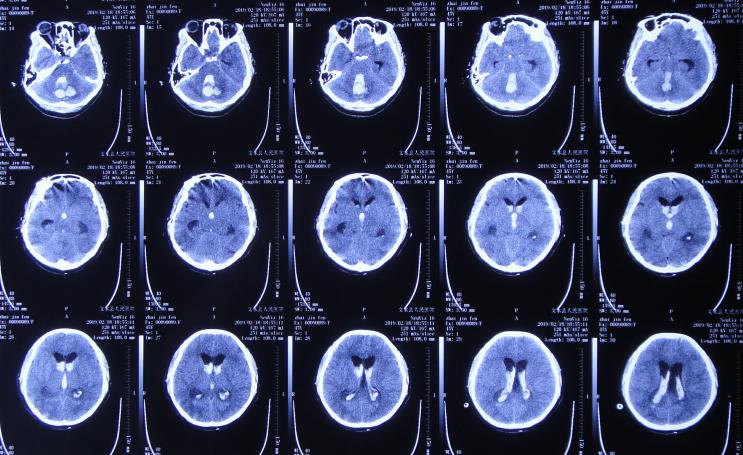

但1小时后出现意识障碍加重,复查头颅CT( 图-2 )示小脑出血增多,急诊进行了左侧脑室穿刺外引流术+后颅窝血肿清除;术后住入重症监护室。

图-2: 2019年2月18日头颅CT02